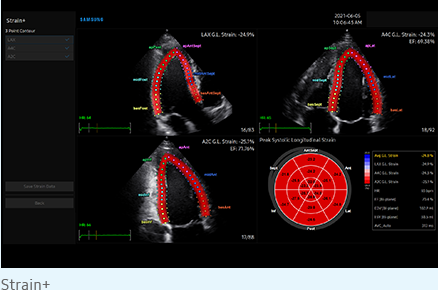

Strain + este un instrument care vă permite să vizualizați și să efectuați o evaluare cantitativă a cineticii peretelui ventricularului stâng (LV). Strain + arată cele trei proiecții standard ale ventriculului stâng și o imagine de tip ochi de taur în format quadscreen, pentru o evaluare ușoară și rapidă a funcției ventriculare.